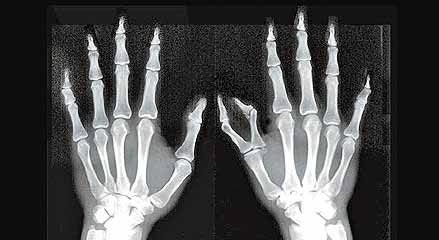

▼他之前晒出自己手部的X光照。